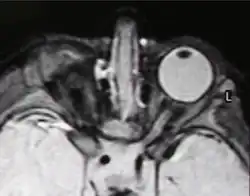

| Right-sided anophthalmia (MR image) | |

MRI/CT

MRIs and CTs can be used to scan the brain and orbits. Radiologists use this to assess the internal structures of the globe, the optic nerve and extraocular muscles, and brain anatomy.